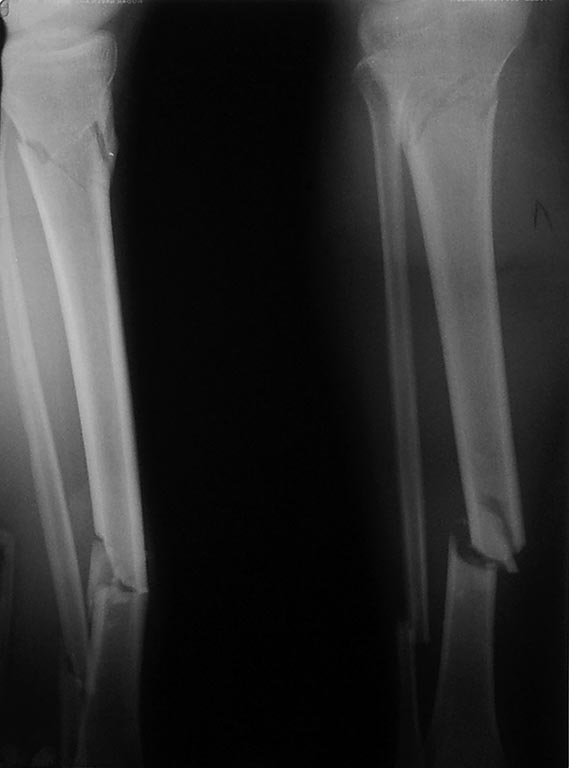

1. В данном случае сможем ли БИОС, если да насколько риск инфекционных осложнений при открытом переломе костей голени.

Надо соблюдать принципы DCO остеосинтез по стабилизации переломов, лучше закрытый, если нет противопоказаний. Хорошо провести УЗИ ротаторной манжеты, при наличии повреждений в переднем отделе - остеосинтез плеча пластиной, при отсутствии стержень или спицы. Голень по желанию. Важно сократить сроки операции и величину кровопотери, минимизировать контаминацию операционного поля - закрытая репозиция малоинвазивный остеосинтез.